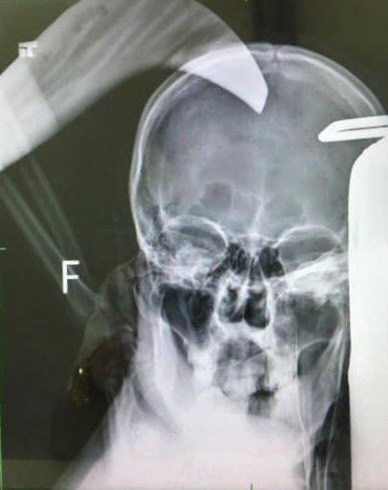

Ngay sau khi phát hiện vụ việc người dân đã báo lực lượng chức năng và nhanh chóng đưa nạn nhân đi cấp cứu tại Bệnh viện Đa khoa tỉnh Quảng Ninh trong tình trạng đa chấn thương vùng đầu, hung khí là con dao dài khoảng 30 cm ngập vào đầu sâu khoảng 5cm, gây rách vỏ não, chảy máu não.

Hình ảnh chụp X- quang nạn nhân bị con dao cắm sâu vào đầu

Các bác sĩ đã tiến hành phẫu thuật bóc tách hung khí trên đầu nạn nhân, xử lý máu tụ, dị vật và mảnh xương vỡ găm vào não. Sau 2h đồng hồ, nạn nhân đã qua cơn nguy kịch và hiện vẫn thở máy.